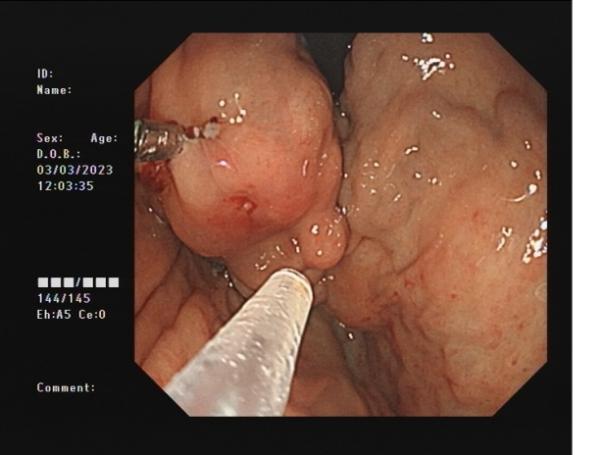

胃底靜脈曲張 內鏡下組織膠粘合術

胃底靜脈曲張組織膠粘合術(HI):治療胃底食管靜脈曲張,防止靜脈曲張破裂出血,降低因肝硬化導致胃底靜脈曲張破裂引起的致命風險。